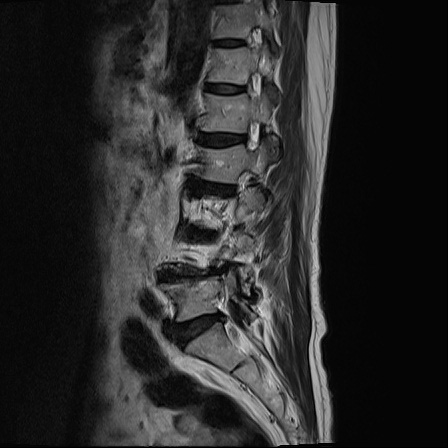

Ӵϲ ɿ ô ô 㸮 ٸ ̾ϴ. ϵ Ͻð ܻ 㸮 20⵿ ͽϴ. mri ˻ ɿ Ȳ ʹ ؼ Ȳ̶ ߽ϴ. ϻȰ ϰ 鼭 ½ϴ. ̴ ø鼭 Ͻô Ȳ ̷ ġ ص ȸ ϴ. δ Ҵµ, ù ȸԲ ˷ֽ ϰ β ϰ, ˷ֽ ü ƮĪ ϸ鼭 ȭǸ鼭 Ӵϲ ȸų ְ ǰ, β 鼭 ʴ β ؾϴ ŷο 1ϸ ijħ ڸ ǥ Ʈ ߽ϴ. ȸ ȭϽø鼭 Ϸ簡 ٸ ȸǽð 4ְ Ǿ Ǯ鼭 ¦ ҽϴ. ħ ȸ ȭϸ鼭 ڼ ü ƮĪ ϴ. ȥڼ Ͻʴϴ. ٳø鼭 ó Ͻ ʴϴ. ̾ ְ ̳ ߵ ʰ ϴ ȸԲ Ͻʴϴ. ʹ ϸ鼭 ϴ. Ȩ - ϱ ٴ Ȳ MRIԴϴ. |